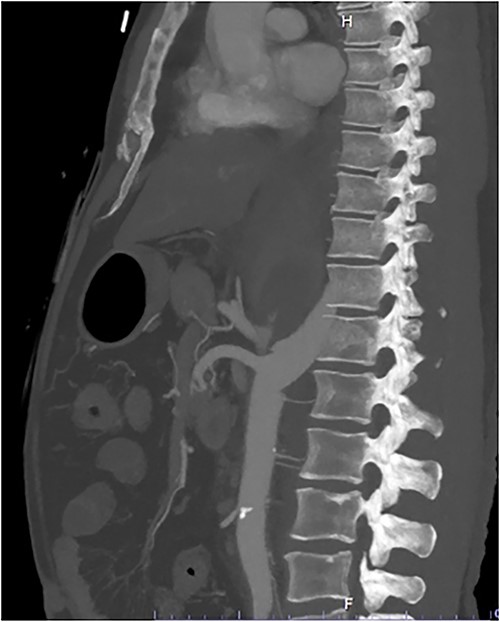

A 54-year-old male presented to our Level 1 Trauma Centre following a high-speed motor vehicle accident with rollover. Although initially haemodynamically stable, significant hypoxia prompted a trauma call activation. On arrival to the Trauma Centre, he had a Glasgow Coma Scale of 8 with an initial heart rate of 70 bpm and systolic blood pressure of 101 mmHg. A brief loss of cardiac output resulted in intubation, bilateral finger thoracostomies and the commencement of massive transfusion. Although his abdominal eFAST was positive, he was fluid responsive and proceeded to imaging. A full computed tomography (CT) trauma series demonstrated CA avulsion (Fig. 1) with contrast extravasation into the retroperitoneum and a large retroperitoneal haematoma measuring 18 cm by 9 cm (Figs 2 and 3). Nil visceral injury was identified and imaging otherwise revealed fractures of the left scapula, right 12th rib and bilateral acetabula and pubic rami.

Axial CT slice demonstrating coeliac trunk avulsion with active bleeding into a large retroperitoneal haematoma.